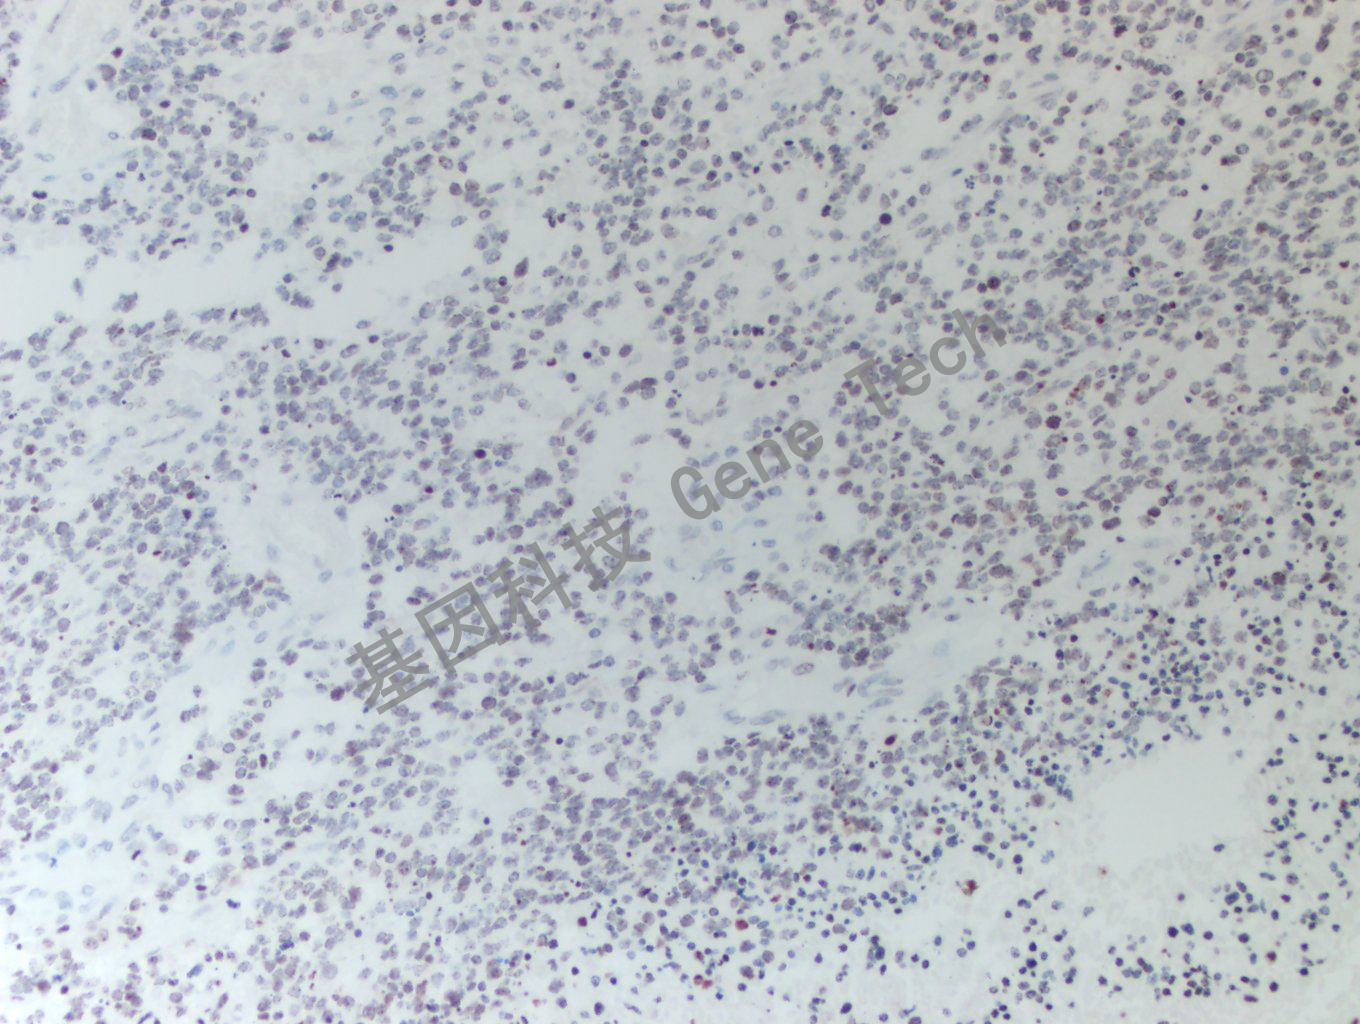

胶质瘤石蜡切片,用 H3K36M(GT2443)染色,细胞核阳性,DAB 显色。